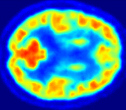

Looking at sample synthetic PET images in Fig. 3, it can be seen that all of the models are able to make reasonable predictions. The outputs of the U-PET and U-PET (no att.) look very similar and are smoothed compared to the input. The pix2pix predicts more details, which seem to be important for the discriminator. However, even though this model has finer predictions, the intensity values are worse compared to the U-PET and U-PET (no att.) as seen in Fig. 2; an example is given in Fig. 3 in the second row.

From a clinical perspective, the synthetic generated PET show a smoother version of the real PET images but keep the same pattern of FDG uptake, especially, hypometabolism in the respective brain areas. This backs up our hypothesis, that MRI contains information that correlates with the functional information of PET images. Moreover, the synthetic PET could be used as complementary visualization for physicians beyond the task of classification.